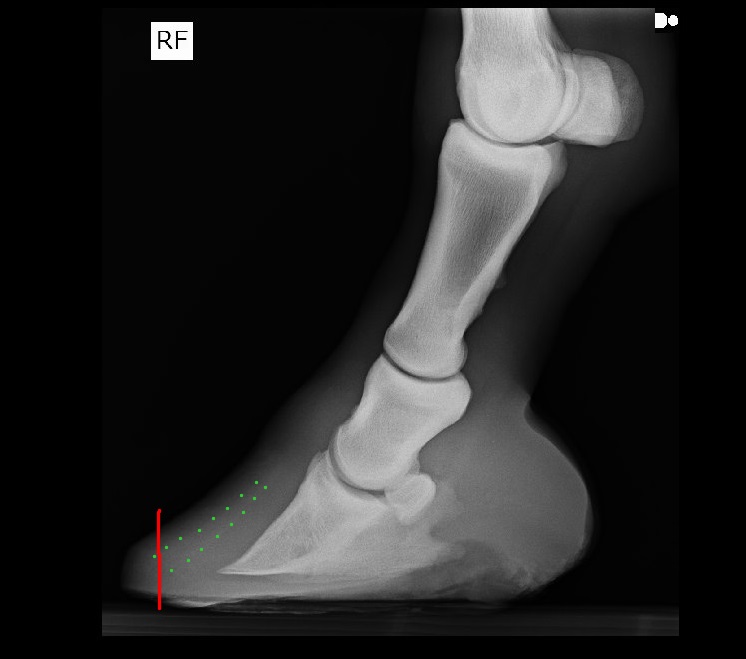

Nutona, вот нарисовала как бы я убирала зацеп.

(зелеными точками обозначила "контур" клина, видно плохо на данных снимках, хорошо бы в программе настройками поиграть, может, станет заметнее)